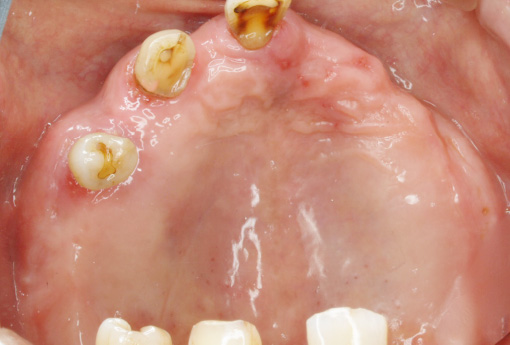

- BEFORE

- AFTER

-